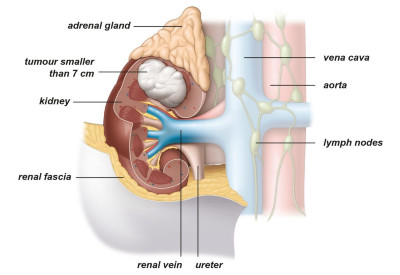

Εντοπισμένο ονομάζουμε τον καρκίνο που εξακολουθεί να περιορίζεται εντός των ανατομικών ορίων του νεφρού, χωρίς να έχει επεκταθεί σε άλλες ανατομικές δομές, όπως λεμφαδένες ή άλλα όργανα (Εικ. 3,4).

Εικ. 3: Όγκος σταδίου Ι

Ο εντοπισμένος καρκίνος του νεφρού μπορεί να αφαιρεθεί είτε μέσω μερικής νεφρεκτομής είτε μέσω ριζικής νεφρεκτομής. Και οι δύο επεμβάσεις μπορούν να πραγματοποιηθούν με ανοικτή, λαπαροσκοπική ή ρομποτική χειρουργική.

Κατά τη διάρκεια μιας μερικής νεφρεκτομής αφαιρείται μόνο ο όγκος (ογκεκτομή), αφήνοντας τον υγιή ιστό των νεφρών ανέπαφο. Αυτή η χειρουργική επέμβαση συνιστάται όποτε είναι πρακτικά εφικτό. Εάν δεν είναι δυνατόν να αφαιρεθεί μόνο ο όγκος και να παραμείνει άθικτο μέρος του νεφρού, τότε η θεραπεία εκλογής είναι η ριζική νεφρεκτομή. Αυτό σημαίνει ότι ο νεφρός στον οποίο βρίσκεται ο όγκος και ο περιβάλλων ιστός αφαιρούνται εντελώς.